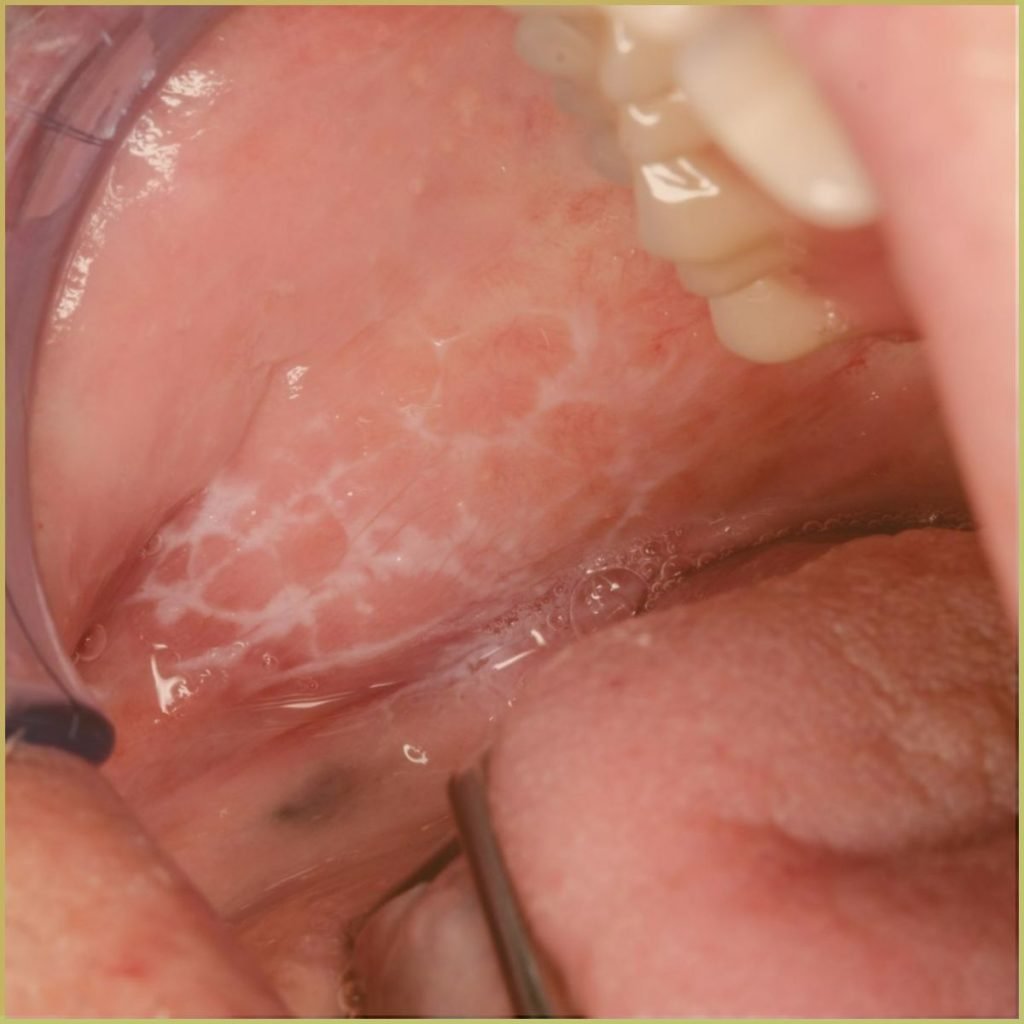

GEOGRAPHIC TONGUE

Geographic tongue (migratory glossitis, erythema migrans) is a distinct condition appearing as a map-like pattern on the dorsum of the patient’s tongue. It is caused by the loss of dorsal papillae, but the reason for depapillation is not well understood. The common clinical presentation includes:

- Focal red depapillated areas bordered by yellowish margins.

- Areas of depapillation may migrate over time.

- Can be associated with fissured (scrotal) tongue.

- Primarily affects the dorsum (top) and lateral borders of the tongue, but can occasionally appear on other mucosal sites, such as the floor of the mouth and cheek mucosa.

- Some individuals may experience mild discomfort or a burning sensation, particularly when consuming spicy, acidic, or hot foods.

- Many cases are asymptomatic, with individuals only becoming aware of the condition during routine dental or medical examinations.

Diagnosis is usually based on the lesion history and clinical presentation alone. Your differential diagnosis should include:

- Lichen planus.

- Lupus erythematosus.

- Candidiasis.

- Psoriasis.

The condition is benign and self-limiting. Topical corticosteroids may be appropriate if the lesion is symptomatic.